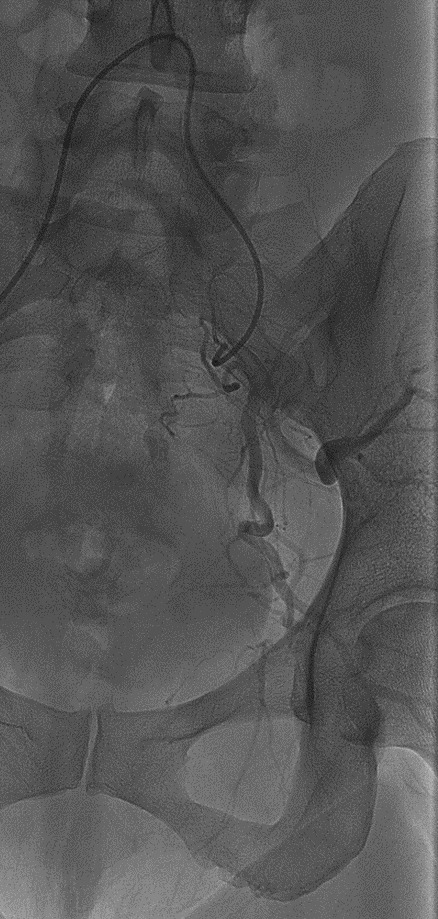

On POD #50 from the hysterectomy, the patient presented to the office with persistent vaginal cuff bleeding, less brisk than prior presentation. There were no sources of bleeding identified on exam. The patient then underwent a CT scan without any evidence of intraabdominal bleeding. Given persistent bleeding without a clearly identifiable source, the decision was made to proceed with bilateral embolization of the anterior divisions of the internal Iliac arteries. The embolization led to resolution of the vaginal cuff bleeding.

This patient’s localized labia minora pain was the result of nontarget labial embolization during bilateral internal Iliac artery embolization. The internal pudendal artery and uterine artery are adjacent to each other, branching off the anterior portion of the internal iliac artery. The internal pudendal artery supplies the labia minora. Most likely, injection of embolic material into the ligated uterine artery resulted in the reflux of particles into the right internal pudendal artery, producing ischemia in the branches supplying the labia.

Labial nontarget embolization was successfully managed with pain medication. This case was interesting because non-target embolization has been reported following uterine artery embolization as a primary fibroid treatment,(Goldberg and Mella 2006) but a literature search found no similar cases in patients who had previously undergone hysterectomy followed by embolization.